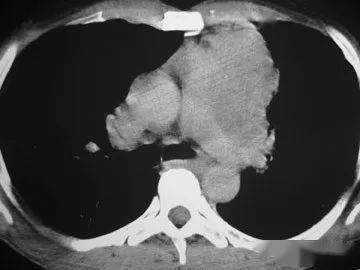

胸腺癌的治療,要根據(jù)TNM的分期來(lái)選擇。術(shù)后治療的選擇,要有明確的病理證實(shí)是R0、R1或R2手術(shù),如果是R1手術(shù),美國(guó)NCCN指南(2012 Version2)推薦術(shù)后放療+化療,R2手術(shù)也如此。關(guān)于是否照射心包,要根據(jù)術(shù)前的CT,看是否有心包受累來(lái)決定。心包的耐受量,三維適形放療(DT45-50GY)應(yīng)該沒(méi)有問(wèn)題,如果長(zhǎng)期生存的年輕者,全心臟的受量要限制在30GY以內(nèi),另外要選擇非蒽環(huán)類的藥物。放療后要補(bǔ)2-3個(gè)療程的化療。